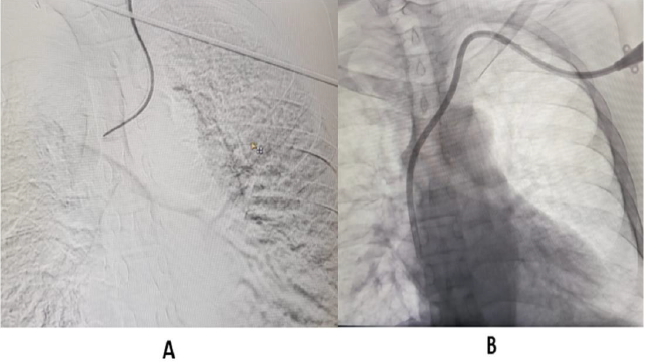

These AVF/AVG take atleast 3-4 weeks to mature. Before AVF or AVG matures, dialysis is done using Tunneled Central Venous Catheter (CVC). Interventional Radiologist (IR) have important role in managing vascular access in patients with CKD. IR secures Tunnelled CVC, preferably through right Internal Jugular vein (IJV), under ultrasound and fluoroscopic guidance, with distal end of catheter, preferably at cavo-atrial junction (Figure 1).

Figure 1:

A. Guidewire in Right internal jugular vein. Also seen is guidewire in central vein, with access from left side.

B. Tunnelled Central Venous Catheter in right internal jugular vein.